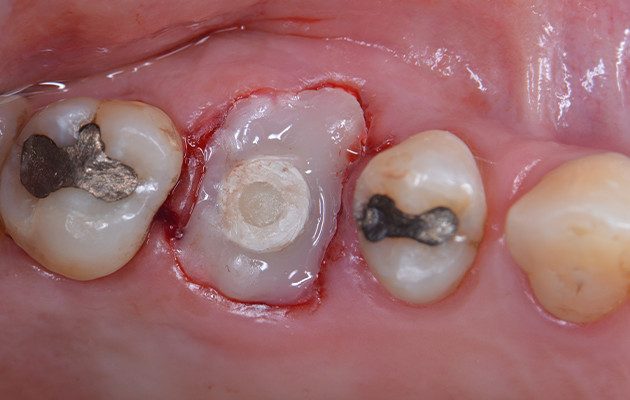

12 | Resina composta fluida unida ao Cicatrizador se estendo até as margens do tecido mole para manter o contorno tecidual durante o período de osseointegração do Implante.

13 | Radiografia periapical realizada logo após a instalação do Implante com Cicatrizador personalizado.